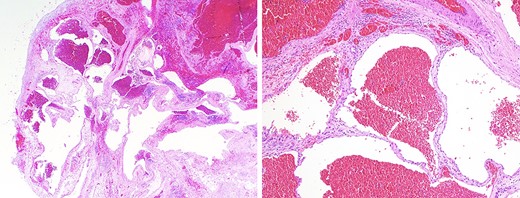

Given her compressive symptoms, interventional radiology (IR) was consulted to drain the presumed cyst to decrease the mass effect on the trachea and allow for safe intubation prior to surgical resection. The procedure was aborted, however, as dense material suggestive of blood clot was encountered by the IR team and there was little free fluid that was able to be drained. Given the significant tracheal compression and risk of difficult intubation, the surgical team coordinated with the extra-corporeal membrane oxygenation (ECMO) team to electively place the patient on veno-venous (VV)-EMCO prior to intubation as previously described [4]. Bilateral femoral veins were cannulated with 23F cannula with VV-ECMO flow initiated at 4 L/min. The patient was subsequently intubated and single lung isolation was obtained. The patient was placed in left lateral decubitus and the case proceeded with a right posterolateral muscle-sparing thoracotomy. Upon encountering the mass, large blood clots were evacuated to decompress the lesion followed by resection; no feeding vessels or point of origin was noted. Estimated blood loss was 100 cc. The patient was decannulated off the ECMO circuit at the end of the case; the duration of ECMO was ~5 h. The decision was made to keep the patient intubated overnight for planned mechanical ventilation and she was extubated without issue in the intensive care unit on postoperative day 1. There was no postoperative clinical tracheomalacia noted. The rest of her clinical course was unremarkable, and she was discharged on postoperative day 5. Final pathology revealed a benign mediastinal hemangioma with intra-cavitary hemorrhage (Fig. 2).

(a) low-power microscopic view (hematoxylin and eosin stain; 20X magnification) showing a well-circumscribed tumor composed of ectatic blood-filled spaces separated by intervening fibrous stroma with scattered lymphoid aggregates, entrapped fat and smooth muscle proliferation; (b) medium-power microscopic view (hematoxylin and eosin stain; 100X magnification) highlighting the presence of endothelial cells lining blood-filled spaces, confirming the diagnosis of a benign hemangioma.

Despite imaging, it may be difficult to differentiate mediastinal hemangiomas from other lesions of the mediastinum without the aid of histopathological confirmation. Histologic features divide hemangiomas into three types: capillary hemangiomas, CHMs, which encompass 90% of cases, and a mixed type [12]. Fig. 2a and2b demonstrates low and medium power views of the lesion, highlighting the presence of endothelial cells lining blood-filled spaces, intervening fibrous stroma, and scattered lymphoid aggregates, diagnostic for CHM. Immunohistochemistry staining was positive for ERD, CD-31, CD-34, confirming a hemangioma and negative for D2-40, effectively ruling out lymphangioma (Fig. 3a and3b).